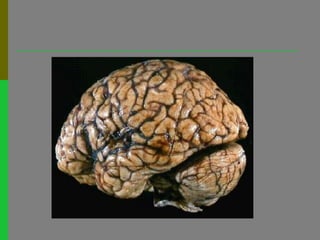

Sistema Nervoso Central

Funções do córtex cerebralÁreas sensitivas(visual, auditiva, gustativa…) – recebem as mensagens sensoriais provenientes dos receptores sensoriaisÁreas deassociação– interpretam a informação recebida e preparam a respostaÁreas motoras– enviam mensagens motoras comandando os movimentos voluntários

Funções do córtexcerebralÁreas sensitivas(visual, auditiva, gustativa…) – recebem as mensagens sensoriais provenientes dos receptores sensoriaisÁreas deassociação– interpretam a informação recebida e preparam a respostaÁreas motoras– enviam mensagens motoras comandando os movimentos voluntários